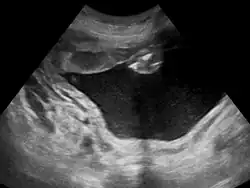

Polyhydramnios is a medical condition describing an excess of amniotic fluid in the amniotic sac. It is seen in about 1% of pregnancies.[1][2][3] It is typically diagnosed when the amniotic fluid index (AFI) is greater than 24 cm.[4][5] There are two clinical varieties of polyhydramnios: chronic polyhydramnios where excess amniotic fluid accumulates gradually, and acute polyhydramnios where excess amniotic fluid collects rapidly.

During the pregnancy, certain clinical signs may suggest polyhydramnios. In the mother, the physician may observe increased abdominal size out of proportion for her weight gain and gestation age, uterine size that outpaces gestational age, shiny skin with stria (seen mostly in severe polyhydramnios), dyspnea, and chest heaviness. When examining the fetus, faint fetal heart sounds are also an important clinical sign of this condition.